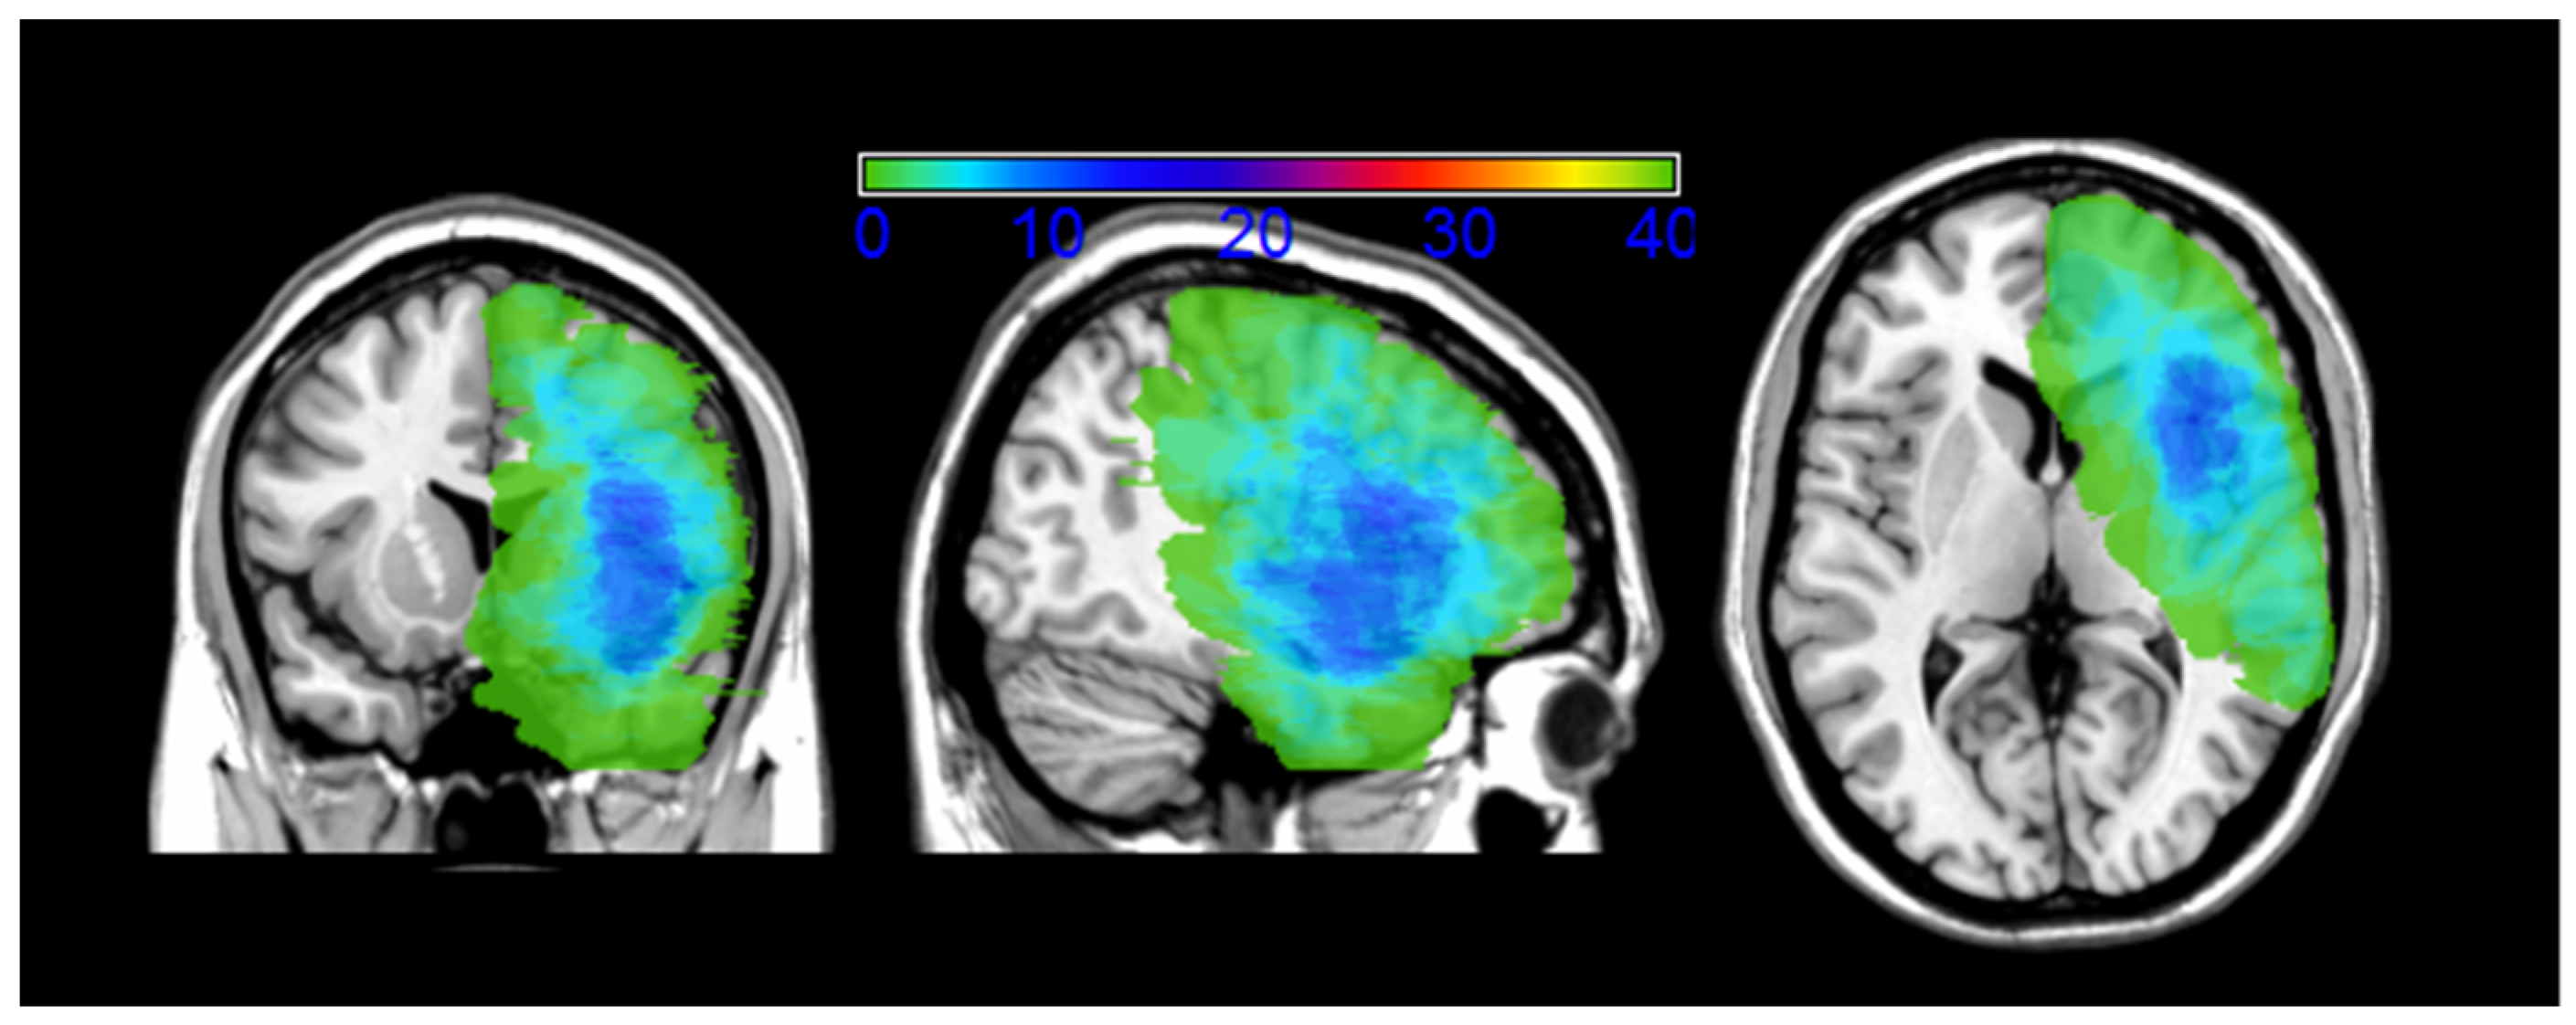

Figure 1.

Overlap of all the 40 pre-recurrence (T3) patients’ lesions masks. Lesion masks include both the surgical cavity of the first surgery and the lesion regrowth. The number of overlapping lesions is illustrated by different colors coding increasing frequencies (as indicated in the bar code). As shown by the image, the epicenter of the overlap is located at the level of the frontotemporoinsular region. MR images are displayed in radiological convention.

Eight gliomas were involved in the fronto-parietal lobe (somatosensory–motor cortex), 23 were in the paralimbic system (9 frontoinsular, 1 temporoinsular, 13 frontotemporoinsular), 5 involved the temporal lobe (operculum), 2 were in the frontal operculum, and 2 were in the temporo-parietal lobe. Figure 1 shows the lesion overlaps. Recurrent lesions were often located both along the walls of and within the previous-tumor cavity (see Figure 2 for a representative case).

Figure 1 shows the overlap of the patients’ lesion masks (lesion masks include both the surgical cavity of the first surgery and the lesion regrowth). This overlay of the patients’ lesion masks shows that the lesions involved eloquent areas. The maximum overlap of the pre-surgical lesion masks, occurring in at least 25% of the patients with recurrence surgery (N = 40), involved the inferior frontal gyrus (pars opercularis). We performed a Voxel Lesion Symptom Mapping (VLSM) analysis trying to correlate lesion location and neuropsychological performance. No significant voxels survived the multiple comparisons corrected threshold.

Structural MRI data processing and statistical analyses were performed using MATLAB r2007b (Mathworks Inc., Natick, MA, USA) and SPM8 (Statistical Parametric Mapping software; Wellcome Department of Imaging Neuroscience, London, UK; http://www.fil.ion.ucl.ac.uk/spm/software/spm8/). Volumes of interest (VOIs) for the patients’ lesions (lesion masks include both the surgical cavity of the first surgery and the lesion regrowth) were drawn on their T2-weighted MRI scans using the MRIcron software (http://www.mccauslandcenter.sc.edu/mricro/mricron/index.html) and were normalized to the Montreal Neurological Institute (MNI) space using the “Clinical Toolbox” (http://www.mccauslandcenter.sc.edu/CRNL/clinical-toolbox) for SPM8.

The MRIcron procedure (http://www.mccauslandcenter.sc.edu/mricro/mricron/index.html) was employed to overlap the lesion templates. An image was generated, selecting the overlap of the lesion masks (VOIs) for the 40 recurring (T3) patient lesions. The number of overlapping lesions is illustrated by different colors that correspond to increasing frequencies (as indicated in the bar code).